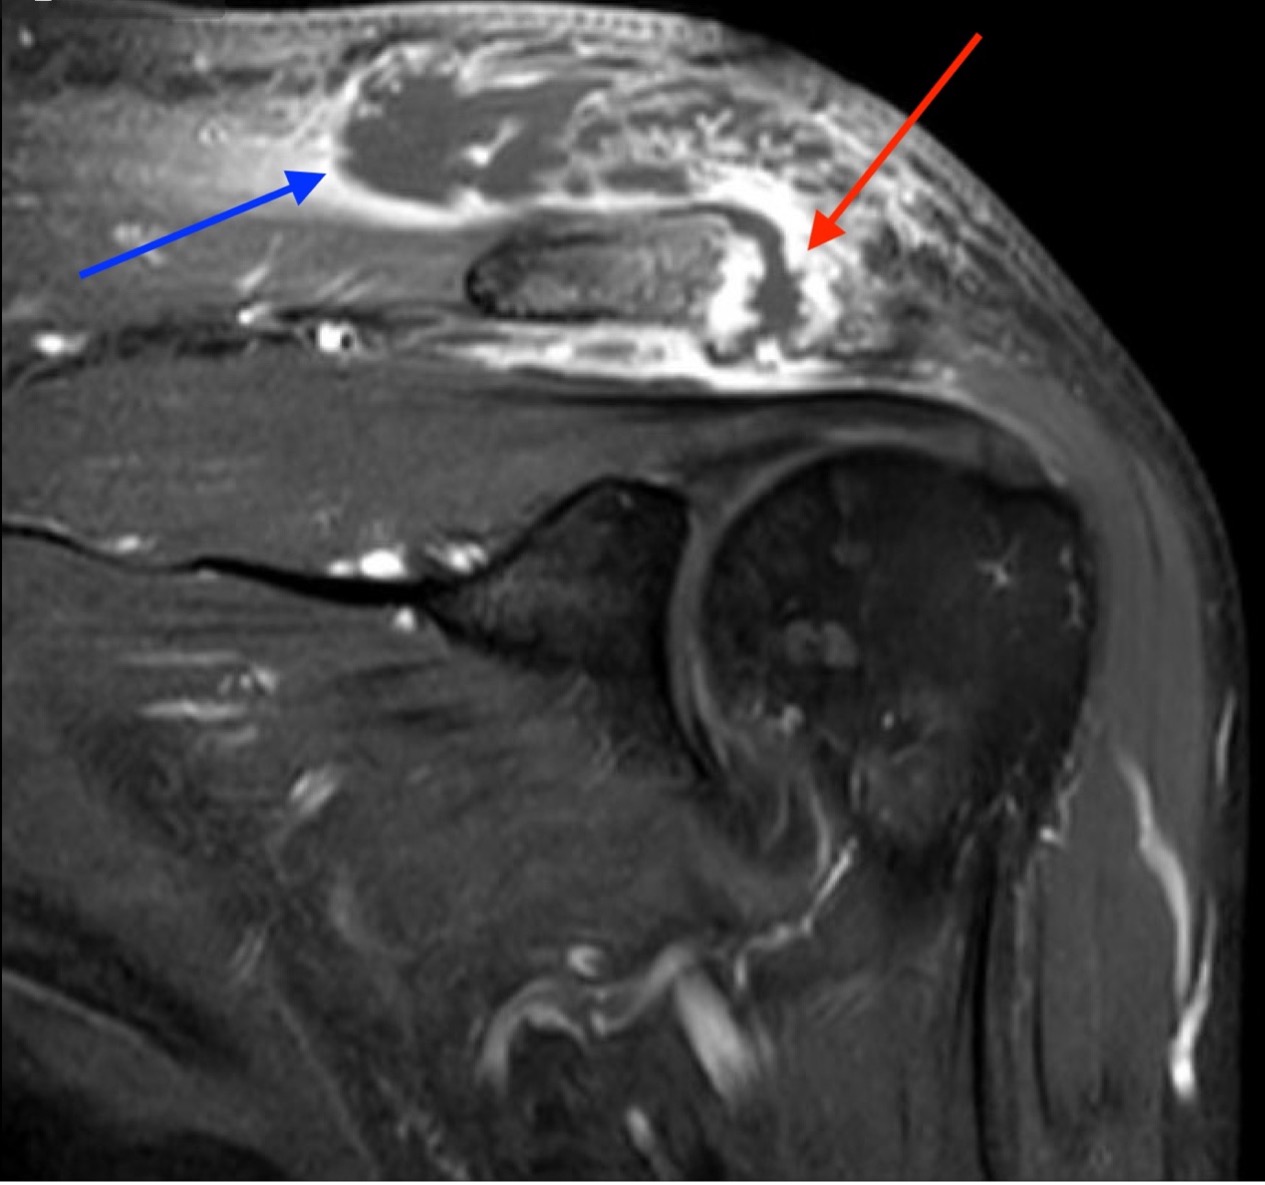

Septic arthritis of native joints is uncommon, but the condition can be threatening to life and limb if left untreated.1 Septic arthritis of the acromioclavicular (AC) joint of the shoulder is particularly rare and has only appeared sparsely in medical literature, mainly through individual case reports. Early recognition and treatment of the condition is vital, but diagnosis of septic AC arthritis can be difficult due to its presentation with vague symptoms and nonspecific laboratory findings. This case report describes the care of a patient with poorly managed diabetes who presented to the emergency department with one month of pain and swelling of the left shoulder and two weeks of pain and swelling in the right ankle. Imaging revealed fluid in the AC joint, and laboratory evaluation showed an elevation in inflammatory markers, including leukocyte count, C-reactive protein (CRP), and erythrocyte sedimentation rate (ESR). The patient's hospital course was complicated by methicillin-sensitive Staphylococcus Aureus bacteremia without evidence of sepsis. The patient underwent open debridement and washout of both the ankle and AC joint without complication. After recovery, the patient was discharged to a rehabilitative center with IV antibiotics and weekly follow up care with infectious disease specialists. This case illustrates the importance of early diagnosis and treatment of septic arthritis, even in less common joint spaces, to prevent progression of this dangerous disease.